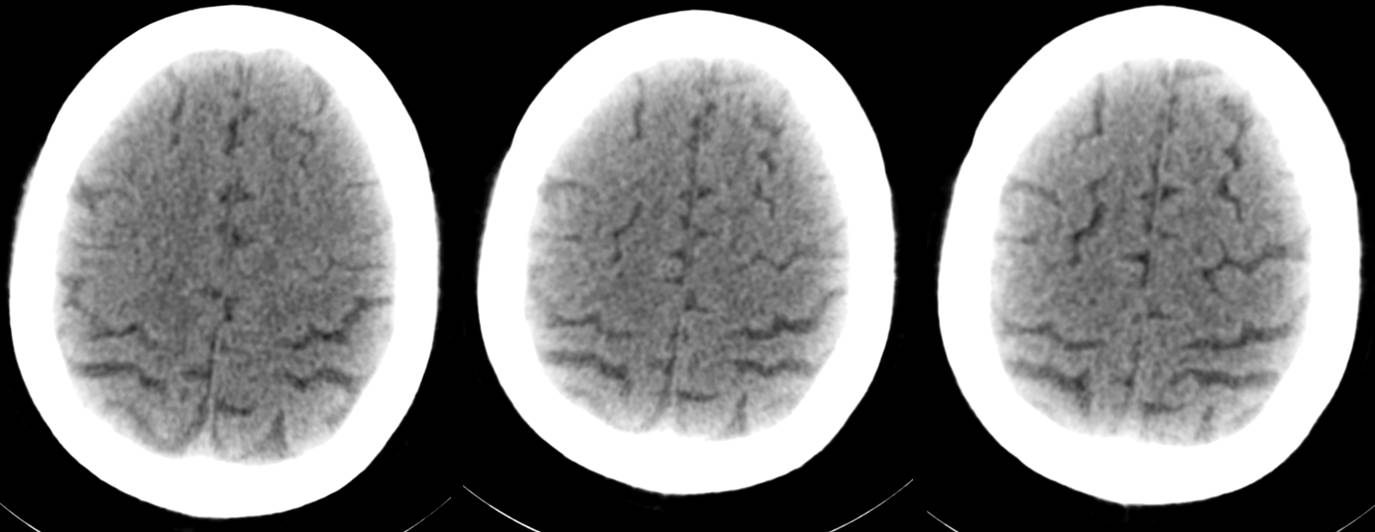

16层移动CT脑部扫描(骨窗像)